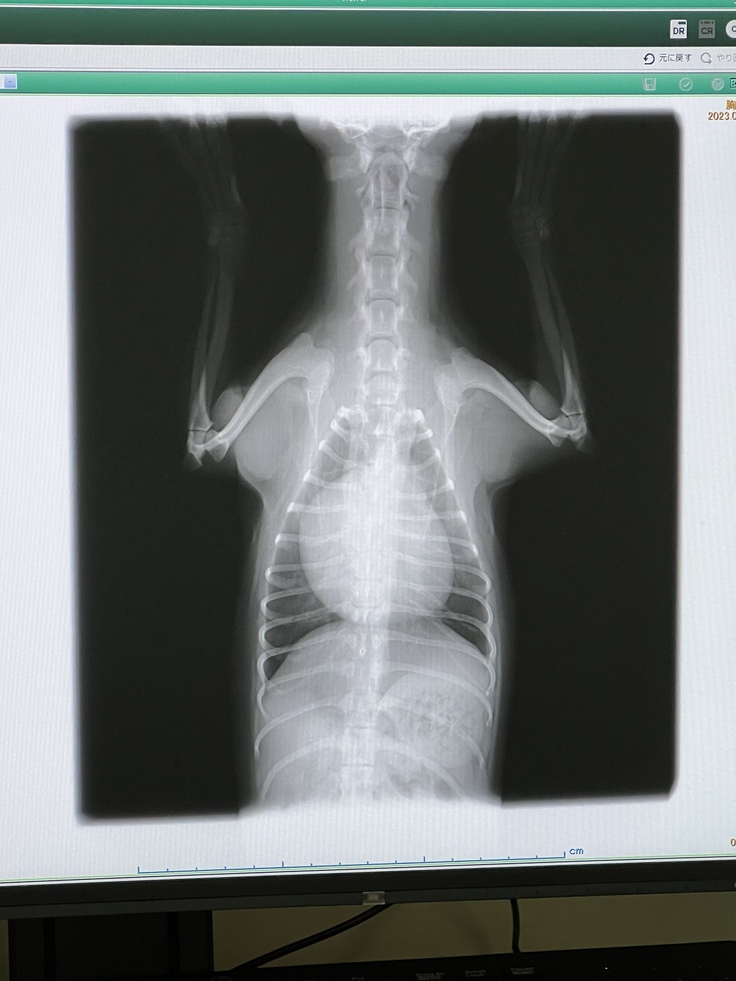

素人の私でもハッキリ分かるくらいレントゲンに写った心臓もかなり肥大しており早期の手術を勧められました。このままだと三尖弁まで影響が出て腹水が溜まり呼吸困難になりやがて死に至ります。今飲ませているお薬はすぐ止めて下さいと。

心臓を止めて人工心肺を使った手術で正午12時から16時の4時間の手術である事と10日間の入院になりますと。レントゲンで心臓がかなり肥大しているのが分かります。